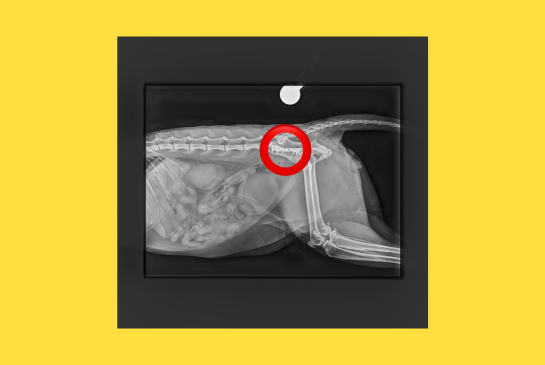

Mondsee/Lochen/Alkoven, 19.2.2026 – Kürzlich hat der Tierschutzhof Pfotenhilfe einen schwer verletzten Kater aufgenommen, der in Mondsee (OÖ) gefunden wurde und ihn unverzüglich zum auf orthopädische Chirurgie spezialisierten Tierarzt Mag. Daniel Eschlböck in Alkoven (OÖ) gebracht. Dieser hat auf den Röntgenbildern multiple Beckenbrüche festgestellt und bereits eine Seite operiert, jetzt folgt die zweite Operation. Die Verletzungen deuten auf einen Autounfall oder Sturz hin. Der Kater ist natürlich stationär bei ihm untergebracht.